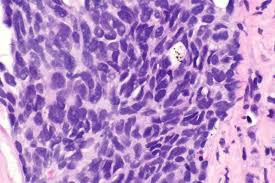

Mobocertinib (Mobocertinib) is a drug used to treat non-small cell lung cancer (NSCLC). It is specifically an oral drug used to treat EGFR gene mutation-positive advanced or metastatic NSCLC.

Mobosetinib is an important treatment option that provides an effective treatment pathway for EGFRgene mutation-positive NSCLC patients, especially those who have developed resistance to other drugs. Patients should closely follow their doctor's recommendations when using the medication and be monitored regularly to ensure safe and effective treatment.